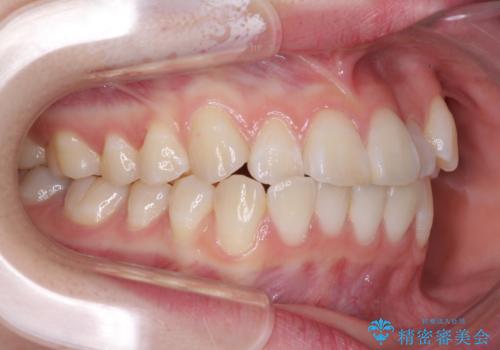

- 海外留学の予定があるが、学生のうちに歯列を整えたいとのことで来院された患者様です。

前歯にデコボコがあり、口元がやや突出した印象があったため、IPR(歯と歯の間を削る)と親知らずを抜歯した上での歯列全体の後方移動をメインに、インビザラインを用いて矯正治療を行うこととしました。